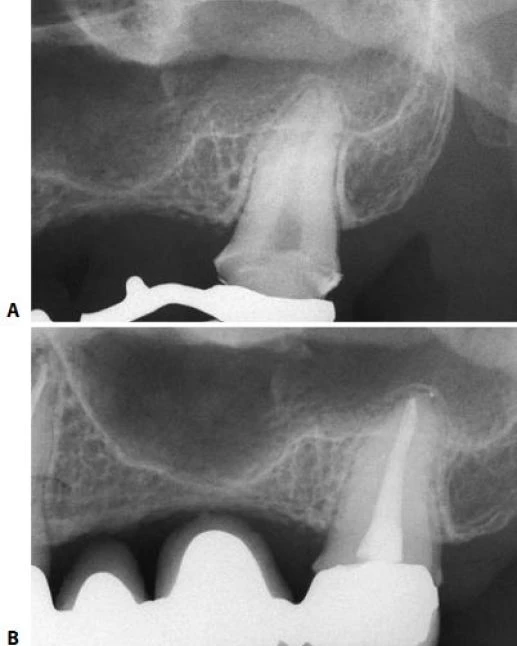

Với 1 buồng tủy hình trứng và 1 sừng tủy, xoang tủy cũng có hình trứng và đường kính lớn theo chiều chóp chân răng –thân răng (hình 11.40). Ở răng này cũng vậy, nếu răng bị mòn hoặc gãy, xoang tủy sẽ liên quan đến mặt nhai (hình 11.41).

Hình 11.41. A. Múi răng nanh trên bị mòn. B. Xoang tủy được mở hoàn toàn ở mặt nhai